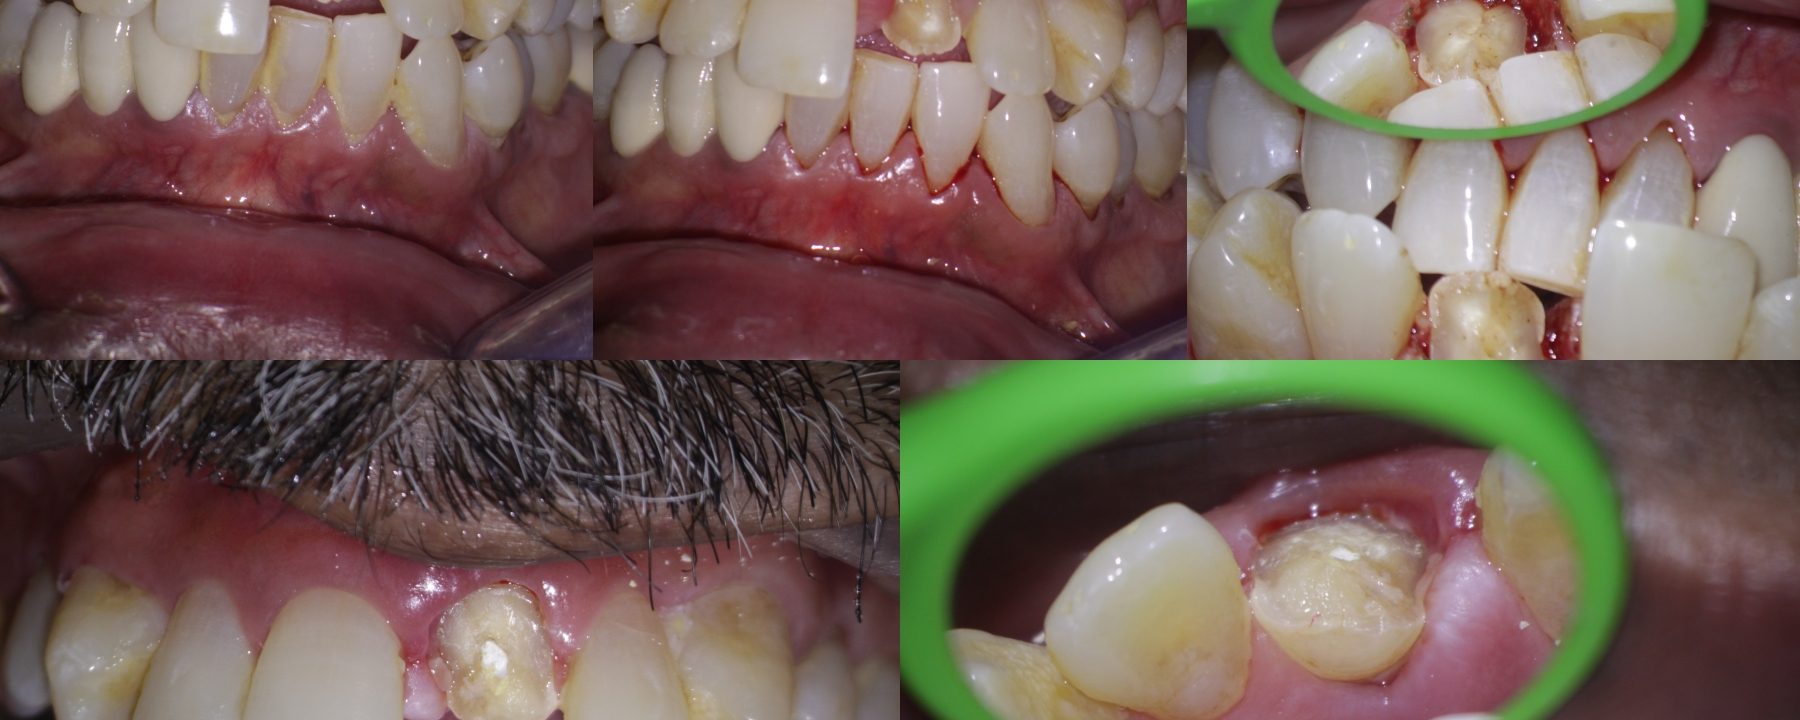

Crown fracture extending sub-gingival

Pt 55 yoM presented with fracture of #9.  History of trauma 2 wks back and was aymptomatic. Gingivectomy using electrocautery was done. Root canal therapy was completed after intermittent CAOH dressing , fibre post cemented and composite build up was done.